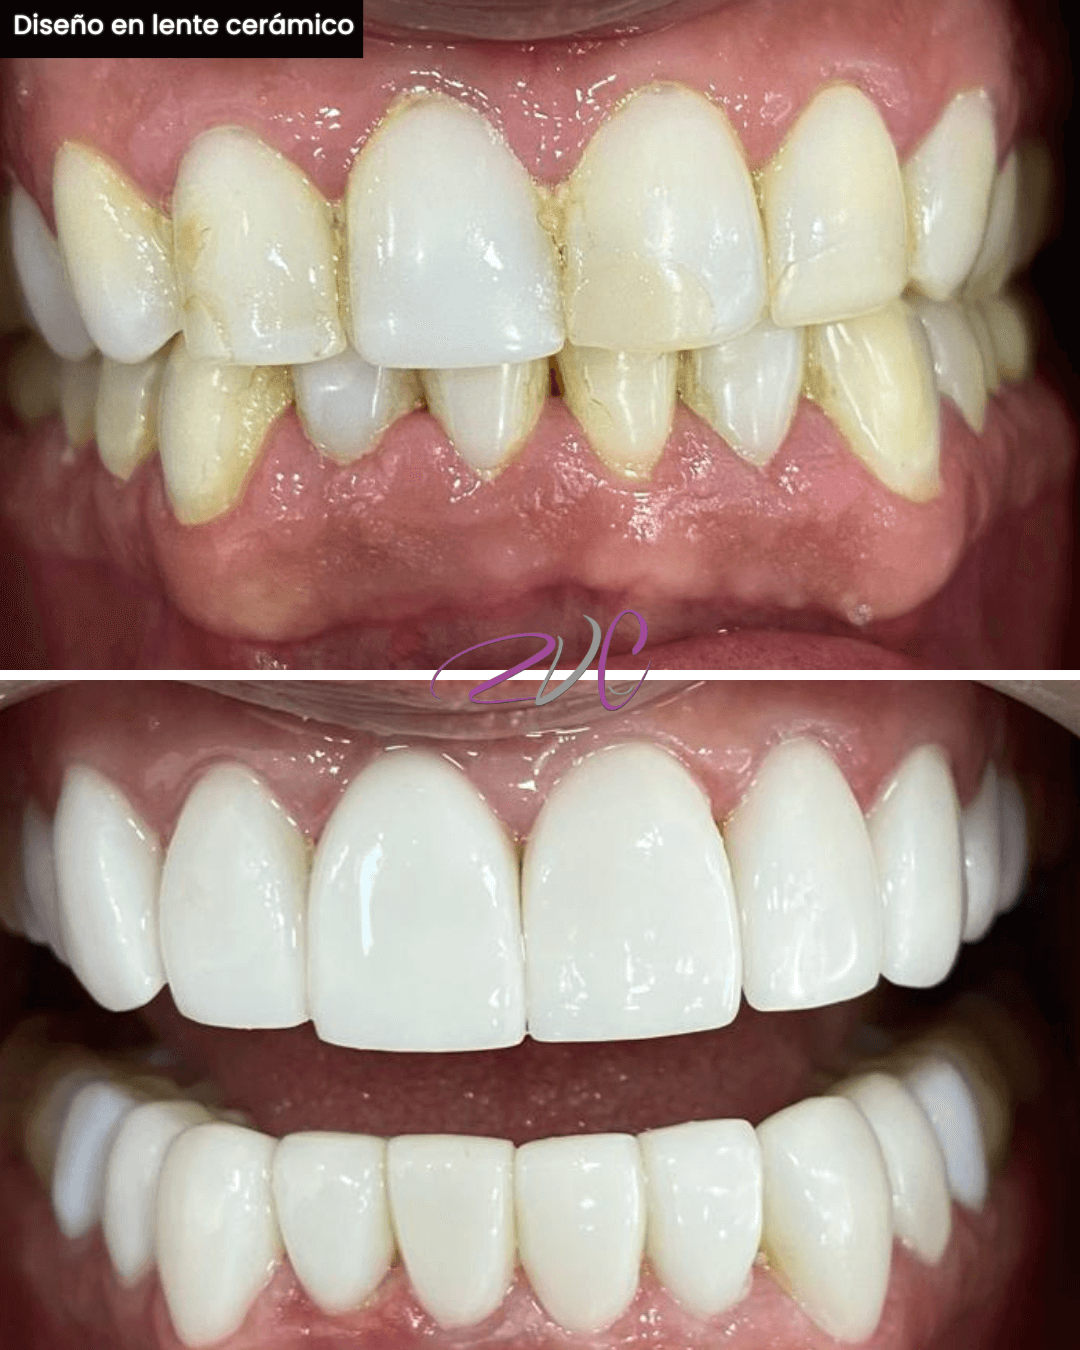

Odontología Estética

Conjunto de procedimientos que armonizan la sonrisa, mejorando su forma, color y alineación. Incluye diseño de sonrisa en resina o lente cerámico, microdiseño dental, contorneado estético y otros tratamientos personalizados según tu tipo de sonrisa.